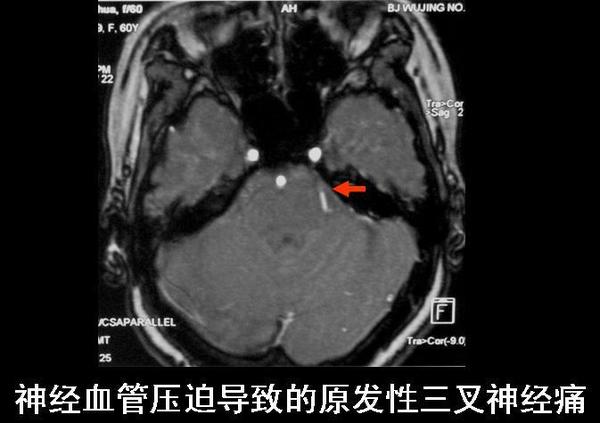

三叉神经痛分为“原发性”和“继发性”两种。首都医科大学宣武医院神经外科梁建涛

一、原发性三叉神经痛:找不到确切病因,较为常见。